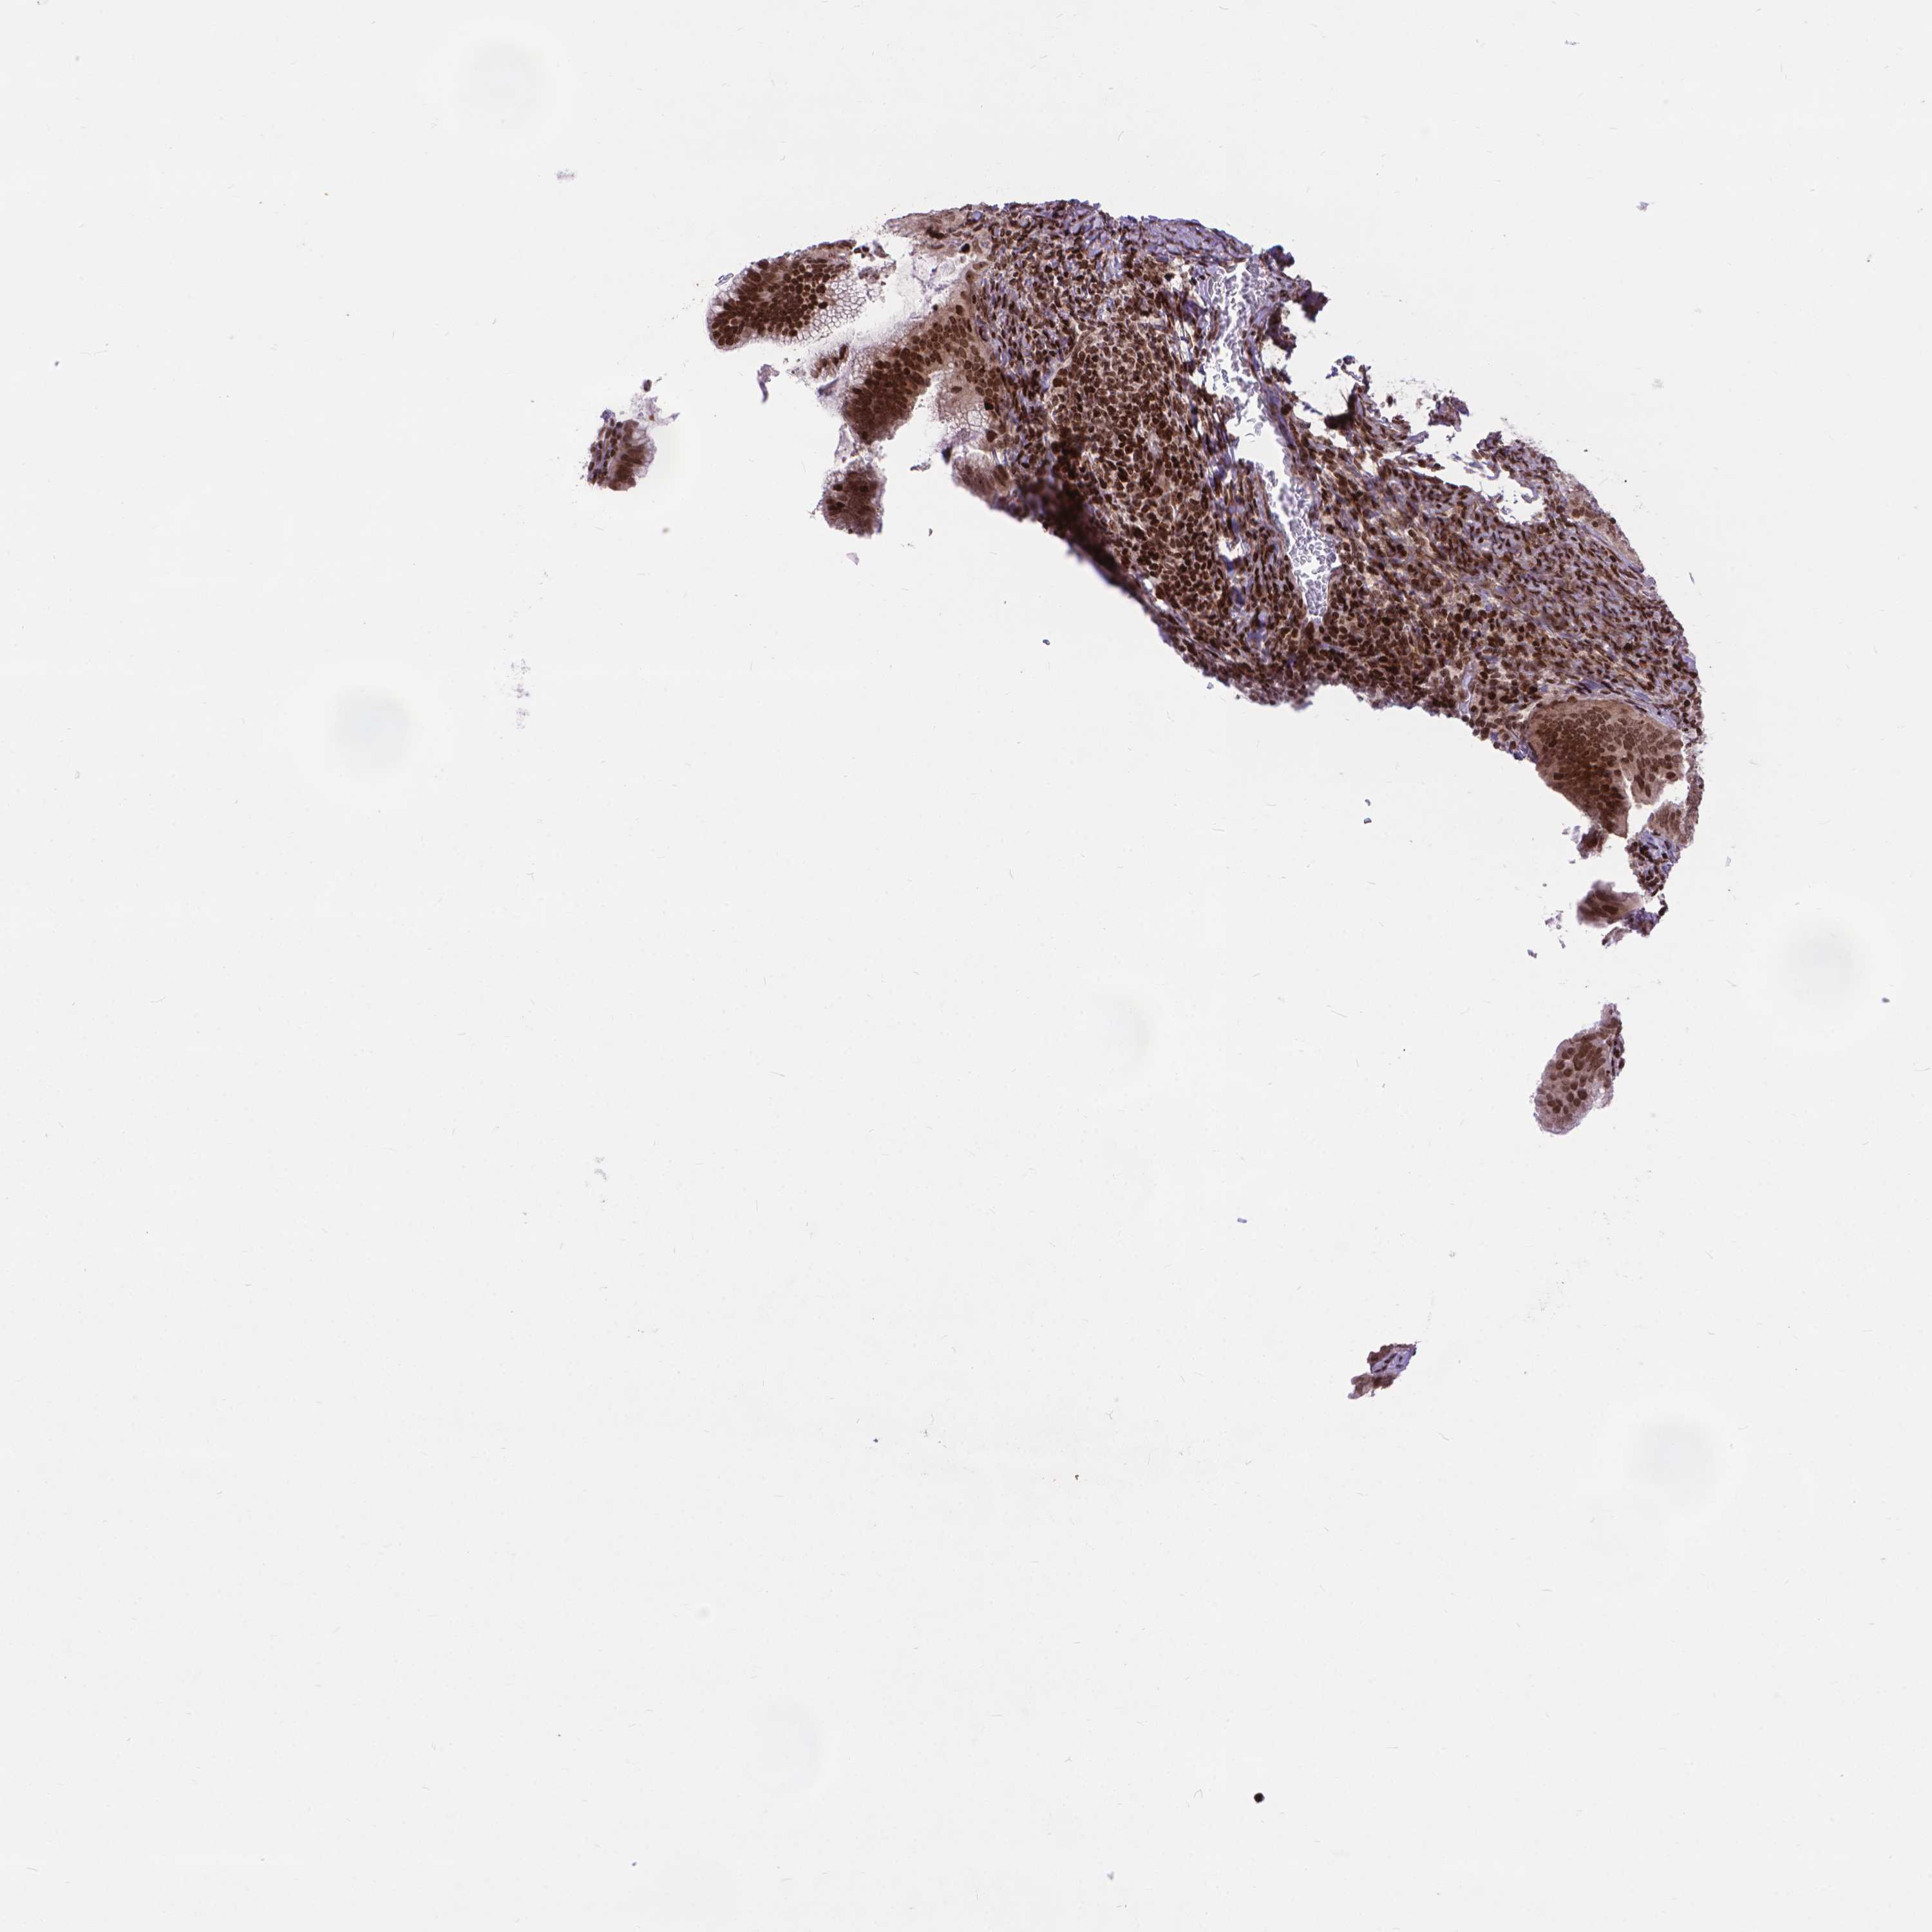

CERVICAL CANCER - Protein expressioni

A mouse-over function shows sample information and annotation data. Click on an image to view it in a full screen mode. Samples can be filtered based on level of antibody staining by selecting one or several of the following categories: high, medium, low and not detected. The assay and annotation is described here.

Note that samples used for immunohistochemistry by the Human Protein Atlas do not correspond to samples in the TCGA dataset.

Antibody stainingi

Antibody staining in the annotated cell types in the current human tissue is reported as not detected, low, medium, or high, based on conventional immunohistochemistry profiling in selected tissues. This score is based on the combination of the staining intensity and fraction of stained cells.

Each image is clickable and will lead to virtual microscopy that enables deeper exploration of all samples and also displays staining intensity scores, fraction scores and subcellular localization as well as patient and tissue information for each sample.

Antibody HPA065214

Staining

High

Medium

Low

Not detected

Intensity

Strong

Moderate

Weak

Negative

Quantity

>75%

75%-25%

<25%

None

Location

Nuclear

Cytoplasmic/membranous

Cytoplasmic/membranous,nuclear

Squamous cell carcinoma, NOS

Adenocarcinoma, NOS